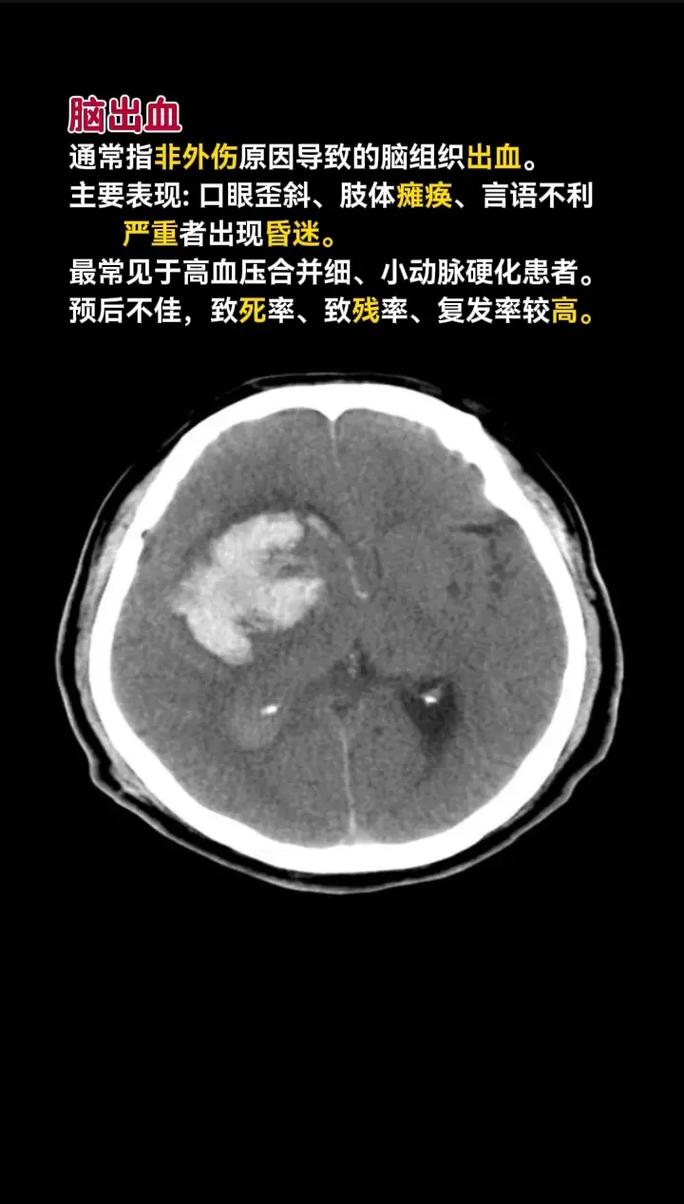

诊断:头颅CT扫描是诊断的关键和首选方法。

- CT表现:在CT图像上,可以同时看到高密度的出血灶(白色区域)和低密度的缺血梗死灶(黑色区域),这是诊断混合性卒中的金标准。